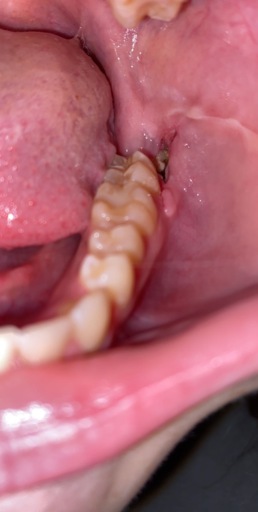

Why is there a bone or tooth coming out of my extraction site?

I had my wisdom teeth extracted 2 weeks ago, and the pain seemed to go away until about a week ago. At first, I didn't see the cause of the pain, but earlier today, I realized that there is something white growing out of my gum. I can't tell if it is a tooth or a bone. What should I do? I've read that they usually fall out on their own, or enter the blood stream, but I'm not sure.

Sometimes when a tooth is removed, the bone that was between the roots is no longer needed and breaks off. It will usually work itself out of the tissue, similar to a splinter. If it becomes uncomfortable, it can easily be removed from the tissue by your dentist. It will not enter the bloodstream and if it is swallowed should not cause any problems until it is discarded on it's own.